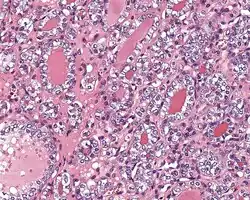

Histologic features

Several specific features must be identified for the tumor to be classified in this new category, while exclusion criteria should also be evaluated.

1) Encapsulated or partially encapsulated. The tumors are usually very well delimited or circumscribed, with the majority encapsulated, surrounded by a well formed fibrous connective tissue capsule.

2) Complete absence of invasion of any kind in a tumor that has been thoroughly and carefully evaluated with the whole capsule of the lesion sampled.

3) Predominantly follicular pattern of growth. Papillary structures should not be present. Further, solid, insular, or trabecular architecture must be <30% of the overall tumor for this category to still apply. Colloid (the material that thyroid follicular cells create) is easily identified throughout.

4) Must have the characteristic nuclear features of papillary thyroid carcinoma, although sometimes the features are patchy in distribution without all of the tumor showing those features. The nuclear features can be divided into three main categories:

- Nuclear size and shape: nuclear enlargement, nuclear elongation, and nuclear overlapping and crowding. Loss of nuclear polarity, with nuclei at the lumen, middle, or basal zone of the cells is also a helpful finding.

- Nuclear membrane irregularities: irregular nuclear contours, nuclear grooves and folds, "rat-bites" or demi-lune formations, and the presence of intranuclear cytoplasmic inclusions.

- Nuclear chromatin characteristics: nuclear chromatin clearing, often with condensation or margination along the nuclear membranes, resulting in accentuated nuclear margins, glassy nuclei, or fine, even delicate, powdery nuclear chromatin.

These features have been recently validated by an international group of practicing general surgical pathologists, showing a substantial interobserver agreement with applying a Nuclear Standardized Scoring System.[18]

- ^ Image by Mikael Häggström, MD. Reference for findings: Rachel Jug, M.B.B.Ch., B.A.O., David Poller, M.D., Xiaoyin "Sara" Jiang, M.D. "NIFTP". Pathology Outlines.